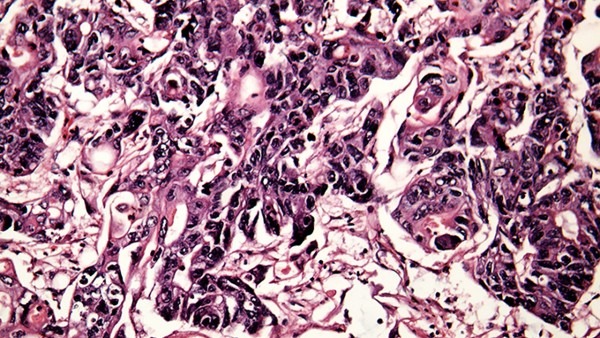

感染后,菌很快经过淋巴系统及血管途径,传递到各器官。通常器官被侵犯后,不一定有临床症状出现。感染后造成阻塞性内动脉炎和周边动脉炎,逐渐形成局部性无痛硬块称为原发性下暗,如不控制将会造成溃疡。

原发性梅毒,也称为下暗,平均在感染后21天出现。下暗部肿大却不痛,并可见火腿到螺旋菌,此时的感染力很强。溃疡常有好几个,主要侵犯到性器官,也可在舌喉,乳房或肛门处发现。由于临床上无痛的病灶,而常被患者忽略了它的严重性。